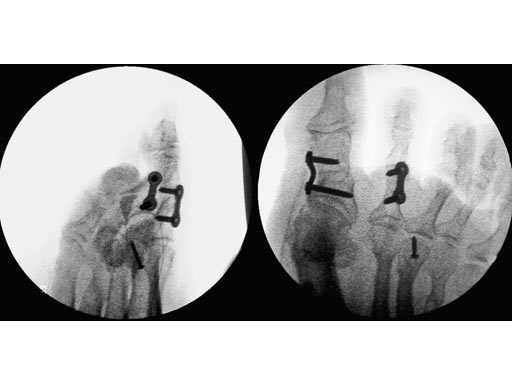

The Locking Two-Hole Plate 2.4/2.7 is indicated for treatment of Akin osteotomy and phalangeal closing wedge osteotomy. It is an addition to the Locking X-Plate 2.7 when a proximal first metatarsal procedure is performed and a counter correction to realign the proximal phalanx is needed.

Correction of malunited Akin osteotomy D1 and shortening of the middle phalanx D2 of a flexible hammer toe using a Locking Two-Hole Plate for each correction.